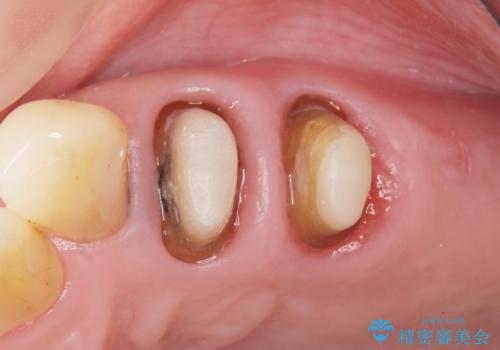

精査したところ、左上の大臼歯2本(左上67)が欠損しており、左上の小臼歯2本(左上45)は根が短く動揺があり根尖病変を認めました。

「大臼歯は入れ歯かインプラントを検討しているがまだやりたくないため、小臼歯のみを治療してほしい」との患者様のご希望により、

相談を重ねた上で小臼歯2本の再根管治療と連結補綴を行いました。

大臼歯がないため小臼歯に負担がかかりやすいことによるリスクを説明し、ご理解頂いた上で治療を行いました。